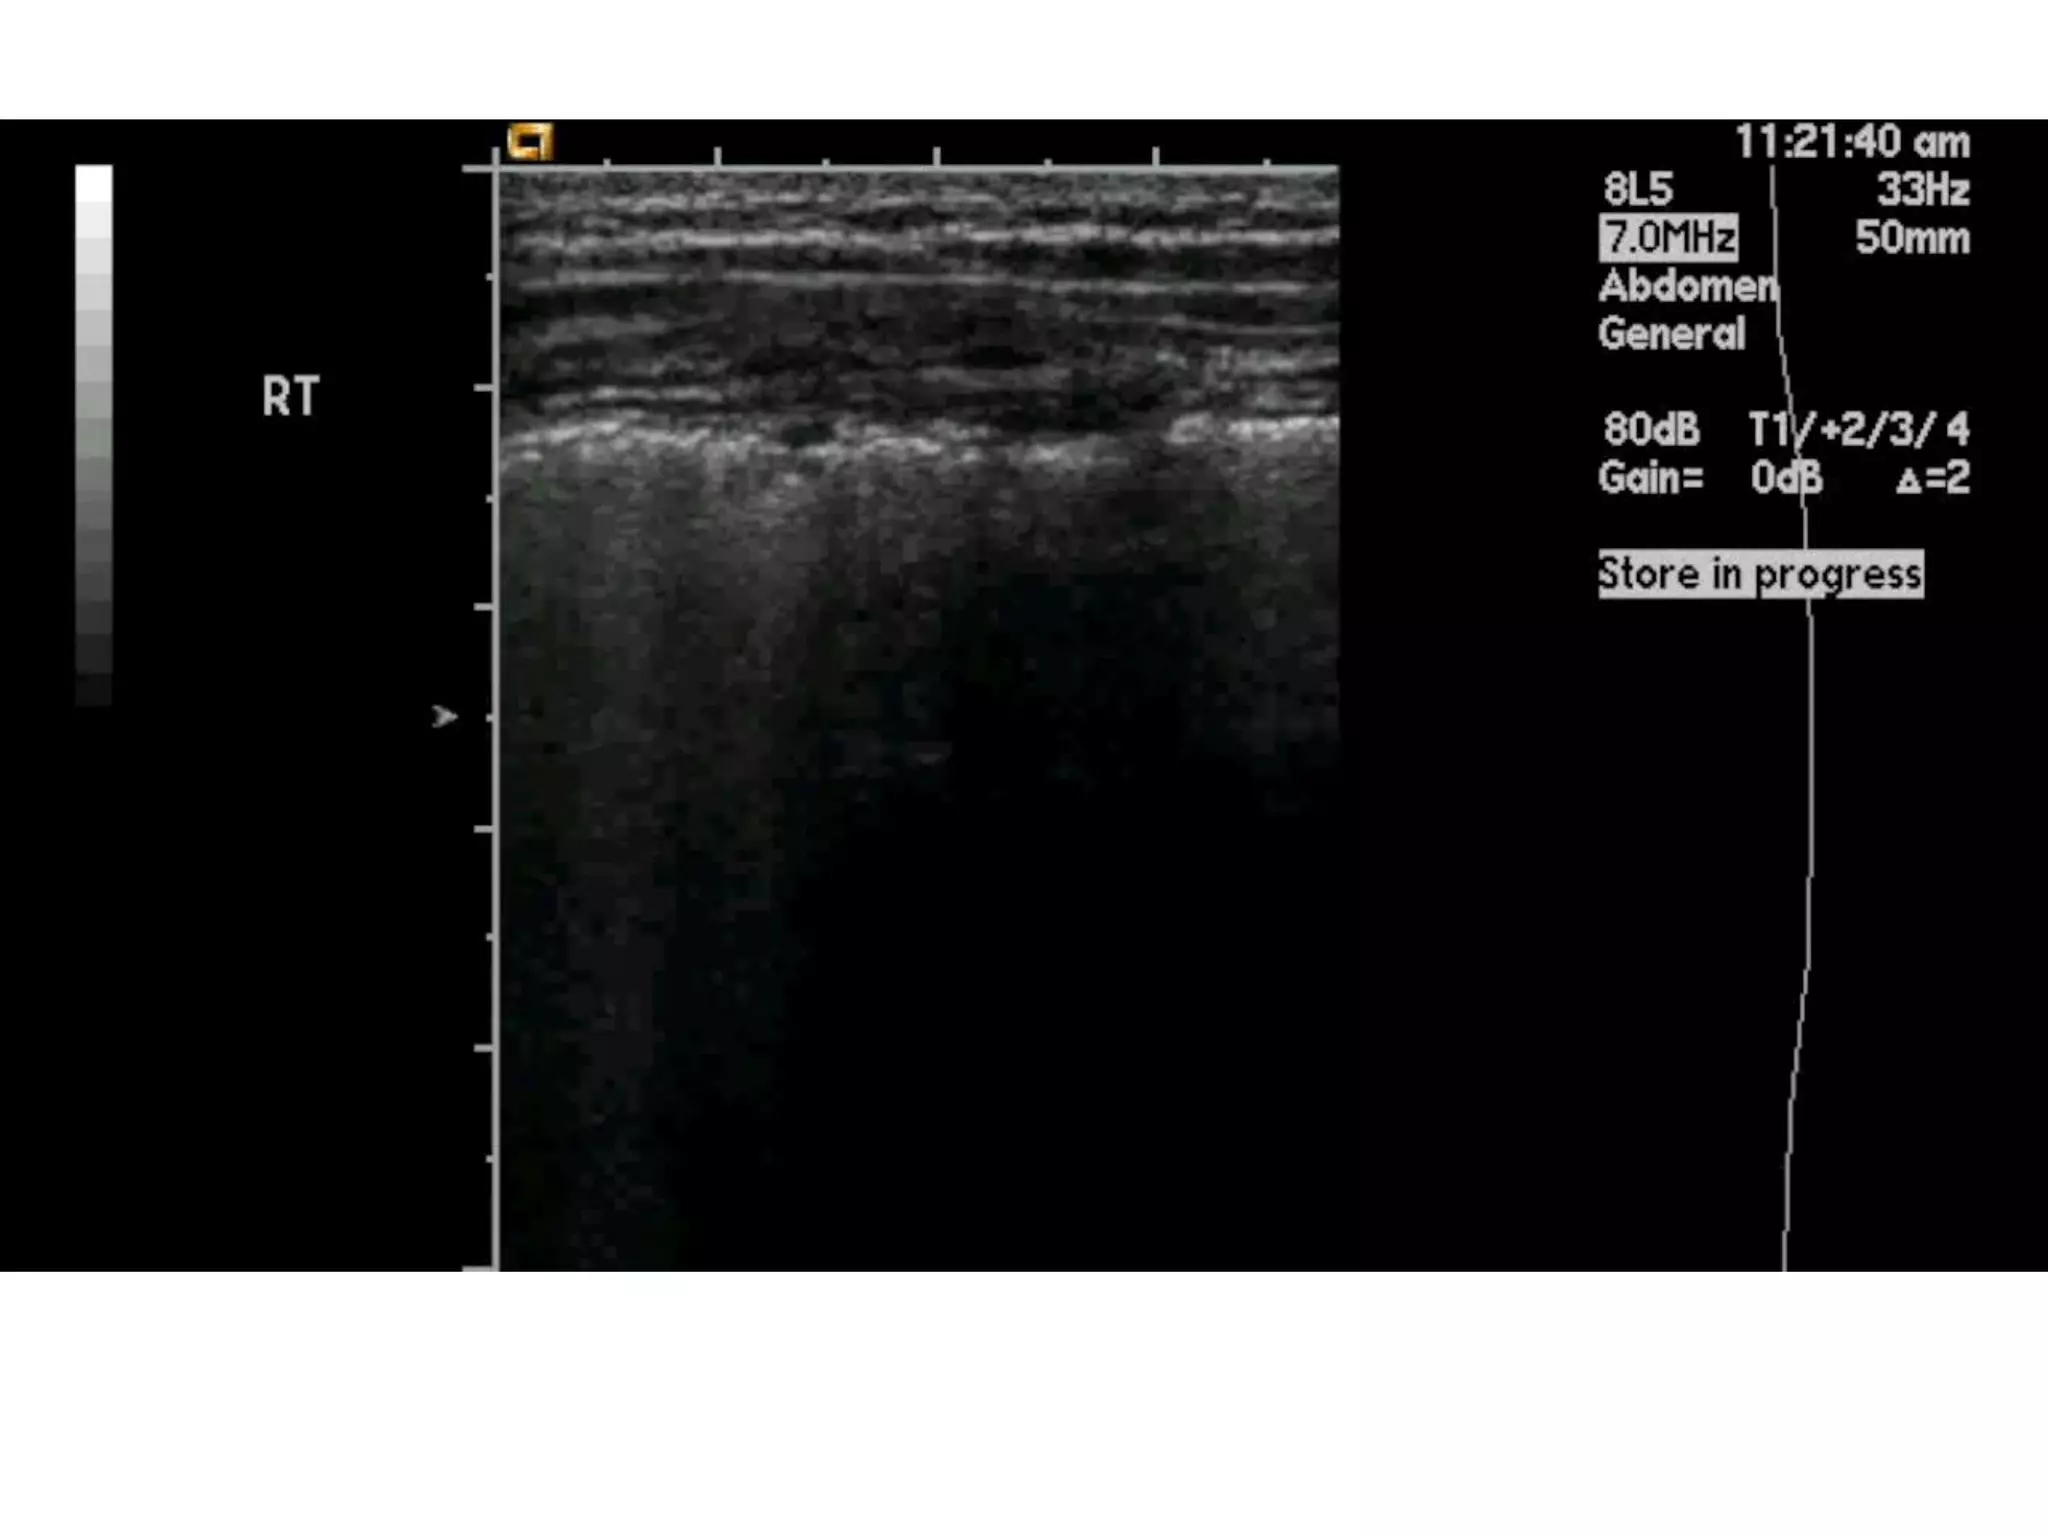

Pneumothorax

• high-frequency (5 MHz) preferred, but

• lower frequency sector transducers / curved

transducer

• placed in the second or third intercostal space

in the midclavicular line in sagittal orientation

moved inferiorly

• oblique fashion

• most helpful - “sliding lung” sign.

• The echogenic line representing the normal

visceral/ parietal pleural interface

• Absence of the normal sliding lung

• M-mode equivalent of lung

sliding  “seashore sign,” and

when absent, the “barcode

sign” is seen corresponding to

• “stratosphere sign.”